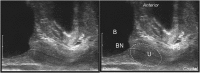

Total pelvic floor ultrasound is used for the dynamic assessment of pelvic floor dysfunction and allows multicompartmental anatomical and functional assessment. Pelvic floor dysfunction includes defaecatory, urinary and sexual dysfunction, pelvic organ prolapse and pain. It is common, increasingly recognized and associated with increasing age and multiparity. Other options for assessment include defaecation proctography and defaecation MRI. Total pelvic floor ultrasound is a cheap, safe, imaging tool, which may be performed as a first-line investigation in outpatients. It allows dynamic assessment of the entire pelvic floor, essential for treatment planning for females who often have multiple diagnoses where treatment should address all aspects of dysfunction to yield optimal results. Transvaginal scanning using a rotating single crystal probe provides sagittal views of bladder neck support anteriorly. Posterior transvaginal ultrasound may reveal rectocoele, enterocoele or intussusception whilst bearing down. The vaginal probe is also used to acquire a 360° cross-sectional image to allow anatomical visualization of the pelvic floor and provides information regarding levator plate integrity and pelvic organ alignment. Dynamic transperineal ultrasound using a conventional curved array probe provides a global view of the anterior, middle and posterior compartments and may show cystocoele, enterocoele, sigmoidocoele or rectocoele. This pictorial review provides an atlas of normal and pathological images required for global pelvic floor assessment in females presenting with defaecatory dysfunction. Total pelvic floor ultrasound may be used with complementary endoanal ultrasound to assess the sphincter complex, but this is beyond the scope of this review.